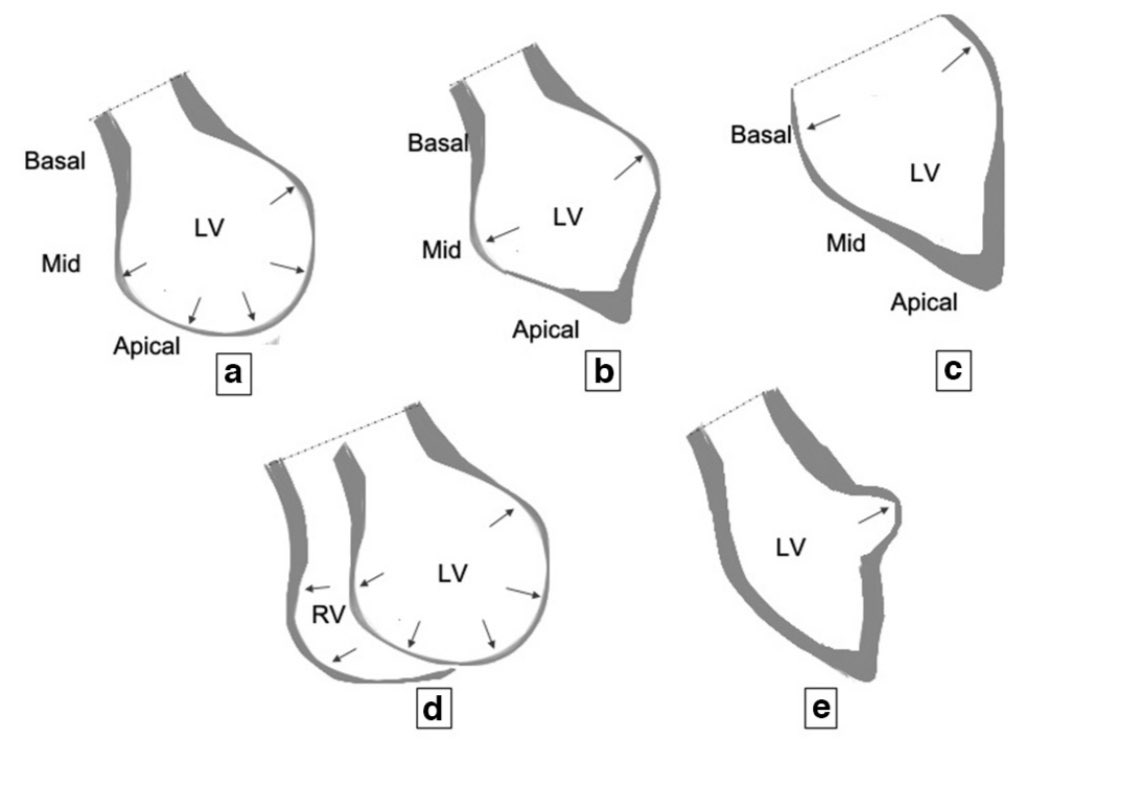

transient LV dysfunction  most commonly basal hyperkinesis and mid-apical

most commonly basal hyperkinesis and mid-apical

LV ballooning and hypokinesia (a) other phenotypes may be present (b-d)

other phenotypes may be present (b-d)  diffuse edema/raised T2

transient LV dysfunction  most commonly basal hyperkinesis and mid-apical

most commonly basal hyperkinesis and mid-apicalLV ballooning and hypokinesia (a)

other phenotypes may be present (b-d)

other phenotypes may be present (b-d)  diffuse edema/raised T2